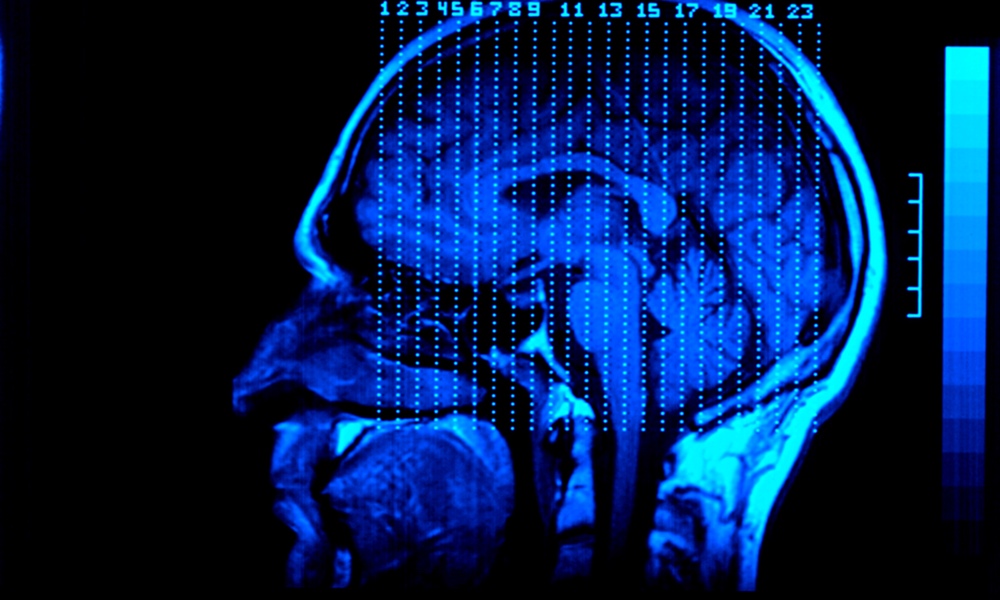

The team used pulses from MRIs spaced at 1,800 pulses per session, 10 times a day spaced 50 minutes apart, over five days to tap into an individual’s neurocircuitry. The MRIs targeted a part of the brain, the dorsolateral prefrontal cortex (DLPFC), associated with cognitive flexibility, working memory and abstract reasoning. Only one participant of an original group of 23 dropped out, due to anxiety, and another was disqualified for having a very high motor threshold (which is related to detecting twitching during an MRI). Each participant had suffered from either bipolar or major depressive disorder for many years.